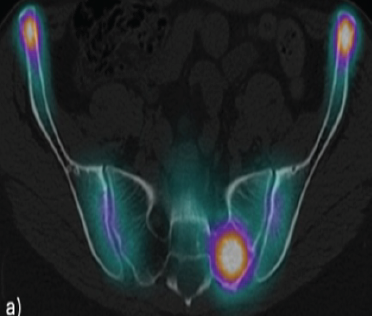

Atypical Hip Pain due to Intra-articular Osteoid Osteoma Treated by Surgical Hip Dislocation in an Adolescent: Case Report

Mario Martínez-Villalobos , Yurik Clemente-Ascencio , Ernesto Roldán-Valadez